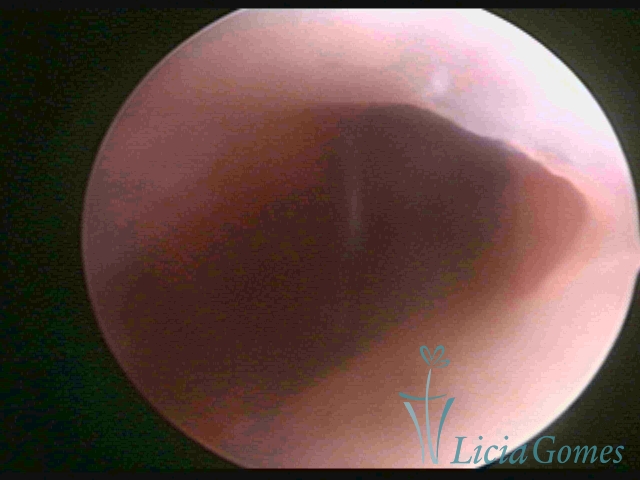

Third part or upper section

Presents the mucosa with a smooth, poorly vascularized surface, to the internal orifice